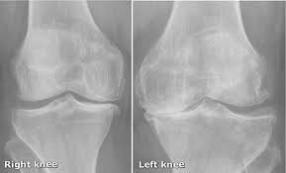

•RTG snimka – pokazuje koštana oštećenja i oštećenja hrskavice kao i prisutnost koštanih izdanaka ( slika 9 )

Slika 9.